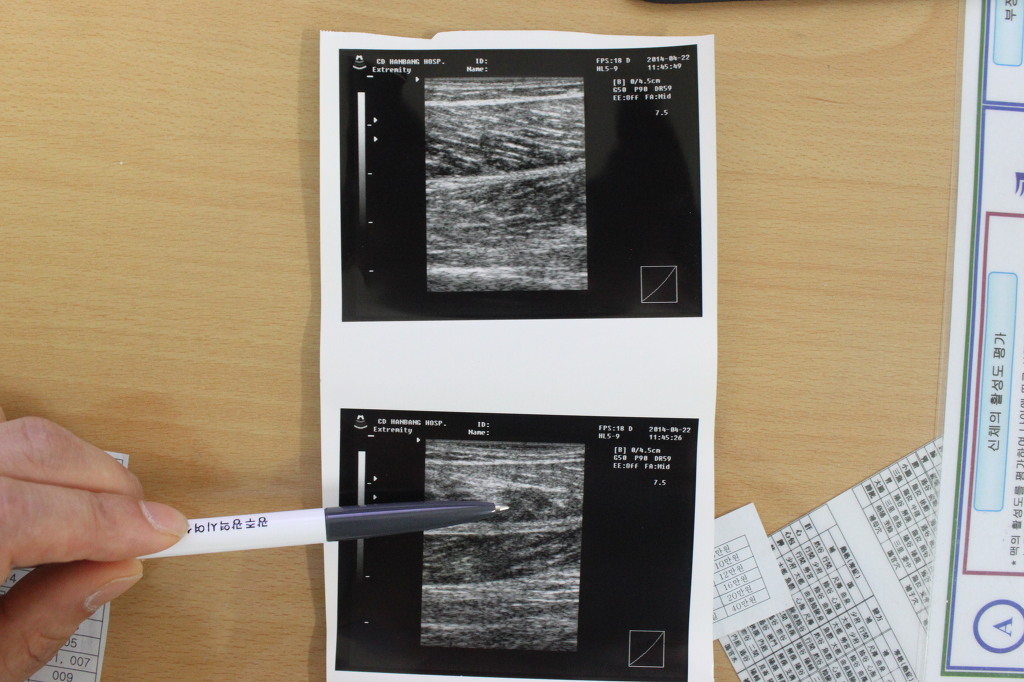

54세 남. 도랑을 건너다 비복근 파열

1. 비복근 파열 위치찾기

3) 근골격계 초음파 동영상